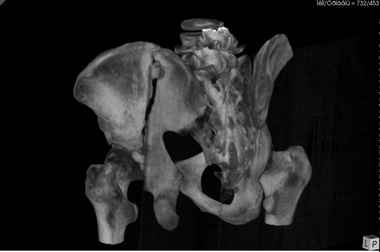

Уважаемые коллеги! В даном конкретном случае речь идет о "ложном суставе", поэтому показано реконструктивно-восстанвоительная операция т.е. остеотомия по линии "ложного сустава" затем остеосинтез реконструктивными пластинами, мы выбрали пахово-подвздошный (с наружным) доступ т.к. линия излома проходит на крышу вертлужной впадины. С уважением Ерсин Жунусов

Андрей, на 3d снимках не видно соотношение суставных поверхностей, величину диастаза в ложном суставе и состояние головки (может уже протез нужен).

Если конгруэнтность и покрытие неплохие надо добиться сращения без репозиции (это тоже не просто, т.к. мышцы будут раскачивать крыло и ломать конструкции).

Если покрытие или конгруэнтность плохие а головка хорошая самое оптимальное - реконструкция свода и фиксация крыла без репозиции.